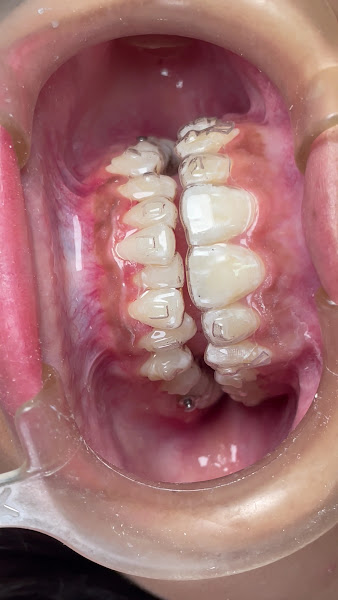

Fotos